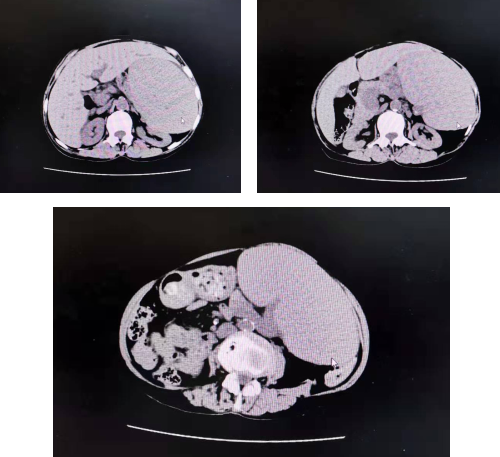

这个夏天,周奶奶一直吃得不多,还瘦了不少,家人还以为老人是瘦夏,直到10多天前,老人摸到自己腹部有一个肿块,还总觉得胃部饱胀,吃一点便胀得难受,连大便都变成黑色的了。家人觉得不对劲,赶紧带老人来必威官方首页官网betway就诊。先在内科挂了号,内科医生初步检查后,将老人转入普外科。普外科李素方主任给老人做了详细检查,老人看上去特别消瘦,左侧肋缘下可以触到巨大脾脏,询问病情,老人最近一段时间饭量一直在减少, 6年前老人在外院就诊时已发现有贫血症状,这些情形引起了李主任的警觉,立即安排老人做上腹部CT,检查结果显示老人脾肿大,脾功能亢进,重度贫血。

“病人特别消瘦,脾脏非常大,巨脾造成病人重度贫血,把胃都挤压到右边来了,病人不能吃饭,一吃就腹胀。这样的重度贫血,仅靠服用补血药物或者输血是很难改善的,所以我们考虑做切除脾脏手术。术前,我们邀请了我院血液科、消化科、心内科、麻醉科主任,进行了一个MDT(多学科会诊)讨论,大家意见一致,切除巨大脾脏,解除它的压迫症状。同时,确定了最优的手术方案及详细执行步骤,以保证手术万无一失。”普外科李素方主任说。

第二天,李素方手术小组为老人进行了巨脾切除术。手术小组打开老人腹腔,发现里面已积聚大量腹水,约1000毫升,吸净腹水后,手术小组细心谨慎操作,顺利从老人腹腔剥离出28cm×17cm大、约7斤重的巨大脾脏。